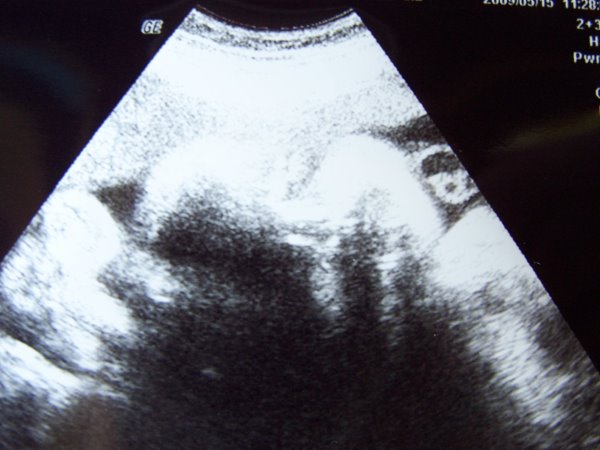

Zsombi pedig oldalról:

Kép